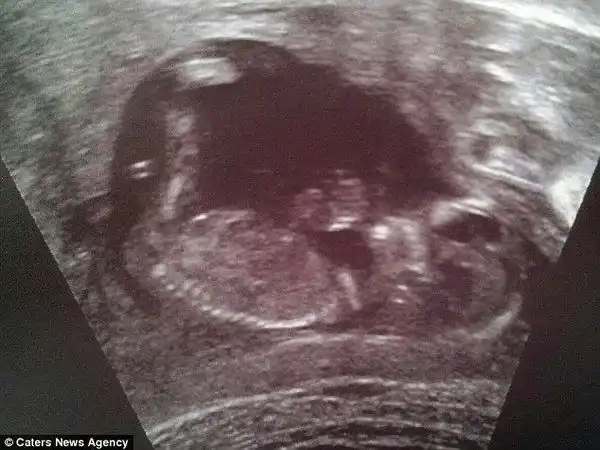

На 20 неделе беременности, Саре сделали узи.

Врач разглядел снимках девочку и он был 100% уверен в своем мнении.